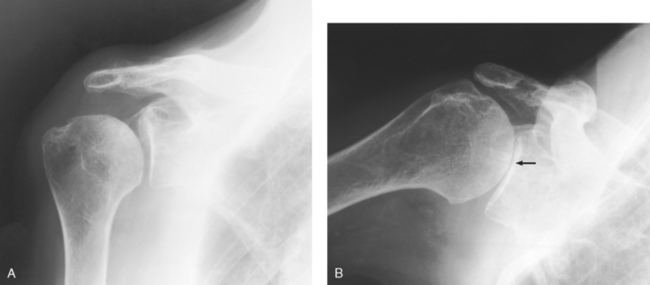

• Anterior dislocation of the humeral head can result in a wedge-shaped compression fracture of the articular surface of the humeral head, called the Hill-Sachs defect.1 The fracture is located on the posterolateral humeral head. An exaggerated external rotation of the arm may be required to see the defect.

Structures shown: An inferosuperior axial image shows the proximal humerus, the scapulohumeral joint, the lateral portion of the coracoid process, and the AC articulation. The insertion site of the subscapular tendon on the lesser tubercle of the humerus and the point of insertion of the teres minor tendon on the greater tubercle of the humerus are also shown. A Hill-Sachs compression fracture on the posterolateral humeral head may be seen using the Rafert modification (Figs. 5-29 and 5-30).

Fig. 5-29 A, Inferosuperior axial shoulder joint: Lawrence method. B, Inferosuperior axial shoulder joint: Rafert modification showing Hill-Sachs defect (arrow). C, Coronal MRI of shoulder joint showing Hill-Sachs defect (arrow) after recurring shoulder dislocation. (A and B, From Rafert JA et al: Axillary shoulder with exaggerated rotation: the Hill-Sachs defect, Radiol Technol 62:18, 1990. C, From Jackson SA, Thomas RM: Cross-sectional imaging made easy, New York, 2004, Churchill Livingstone.)

The West Point1 method is used when chronic instability of the shoulder is suspected and to show bony abnormalities of the anterior inferior glenoid rim. Associated Hill-Sachs defect of the posterior lateral aspect of the humeral head is also shown.

Structures shown: The resulting image shows bony abnormalities of the anterior inferior rim of the glenoid and Hill-Sachs defects of the posterolateral humeral head in patients with chronic instability of the shoulder (Fig. 5-33).